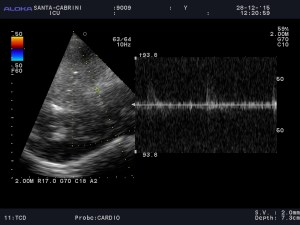

Next, I do trans-cranial doppler (TCD):

Now despite good visualization of brain tissue, specifically brainstem (sometimes difficult in men), I struggle to find any blood flow, and finally manage to see what looks like the basilar artery, and has very poor flow, similar to the EC, with a small systolic peak, retrograde flow and little diastolic flow.

This right away tells us there is a massive ICP elevation explaining the lack of awakening, and a dismal prognosis.